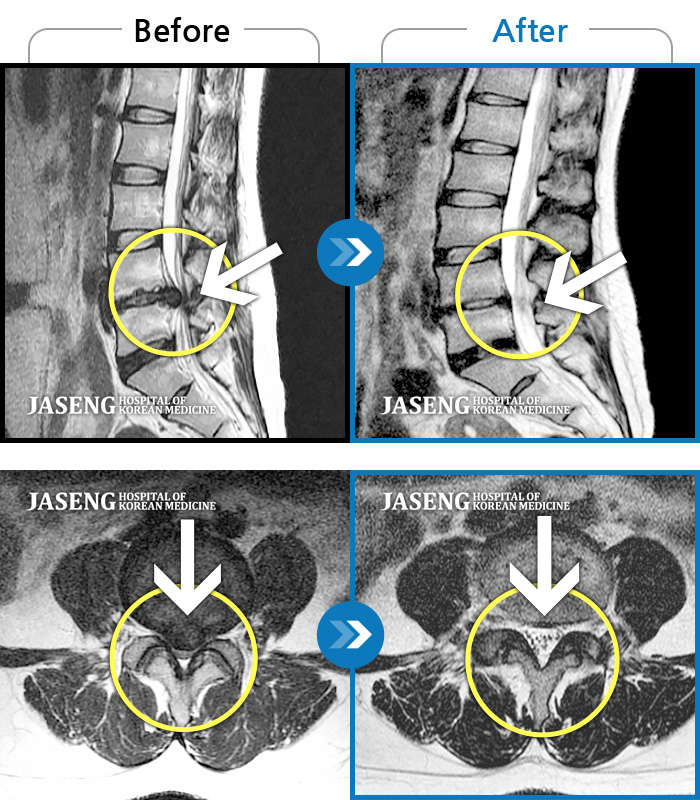

허리디스크

인천 · 조남훈 원장

좌측 허벅지와 종아리가 찌릿하고 묵직한 통증이 있어요.

촬영시기

2025.03.18 ~ 2025.07.22

2025.08.01

조회수 14,275